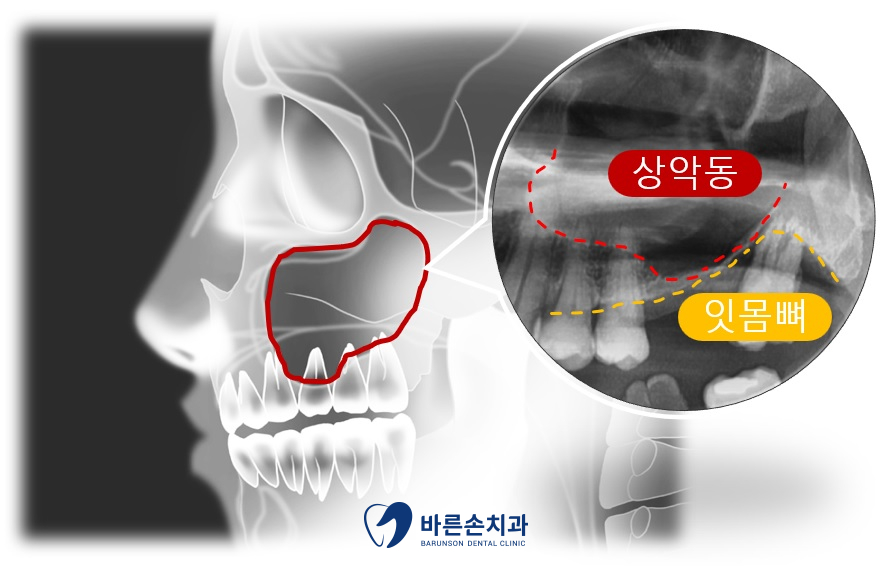

우선 치아의 뿌리와 치조골 및 전반적인 확인을 위해 파노라마 촬영을 시행합니다

파노라마 판독 결과

1번 치아 뿌리에 파절이 보이고

2번 치아에는 치조골 손상이 보이네요

<여기서 상악동 거상술이란??>

우선 상악동이란 광대 뼈 속에 위치한 공기 주머니를 뜻하며

위 치아 치주염이 심했던 경우, 이가 빠진지 오래된 경우, 상악동이 쳐져있는 경우

등 다양한 원인으로 상악동이 내려와 치조골이 얇아 질수 있습니다

이런 경우 행하는 술식을 상악동 거상술 이라고 합니다